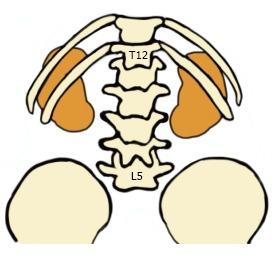

Transforaminal Percutaneous Endoscopic Discectomy (TPED) is a minimally invasive technique mainly used for the treatment of lumbar disc herniation from a lateral approach. Performed under local anesthesia, TPED has been proven to be a safe and effective technique which has been also associated with shorter rehabilitation period, reduced blood loss, trauma, and scar tissue compared to conventional procedures. However, the procedure should be performed by a spine surgeon experienced in the specific technique and capable of recognizing or avoiding various challenging conditions. In this review, pitfalls that a novice surgeon has to be mindful of, are reported and analyzed.

经椎间孔入路经皮内镜下椎间盘切除术(TPED)是一种主要用于从侧方入路治疗腰椎间盘突出症的微创技术。TPED在局部麻醉下进行,已被证明是一种安全有效的技术,与传统手术相比,它还具有康复期短、失血少、创伤小和瘢痕组织少的特点。然而,该手术应由精通该特定技术且能够识别或避免各种具有挑战性情况的脊柱外科医生进行。在本综述中,报告并分析了新手外科医生必须注意的陷阱。